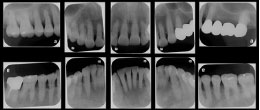

デンタルレントゲン

10枚法

10枚法はお口の中を10ブロックに分け、数本ずつの歯を撮影する方法です。歯1本1本の状態を詳しく診察できます。